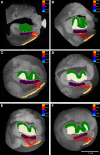

Ex vivo magnetic resonance imaging yields high resolution images that reveal detailed cerebral anatomy and explicit cytoarchitecture in the cerebral cortex, subcortical structures, and white matter in the human brain. Our data illustrate neuroanatomical correlates of limbic circuitry with high resolution images at high field. In this report, we have studied ex vivo medial temporal lobe samples in high resolution structural MRI and high resolution diffusion MRI. Structural and diffusion MRIs were registered to each other and to histological sections stained for myelin for validation of the perforant pathway. We demonstrate probability maps and fiber tracking from diffusion tensor data that allows the direct visualization of the perforant pathway. Although it is not possible to validate the DTI data with invasive measures, results described here provide an additional line of evidence of the perforant pathway trajectory in the human brain and that the perforant pathway may cross the hippocampal sulcus.